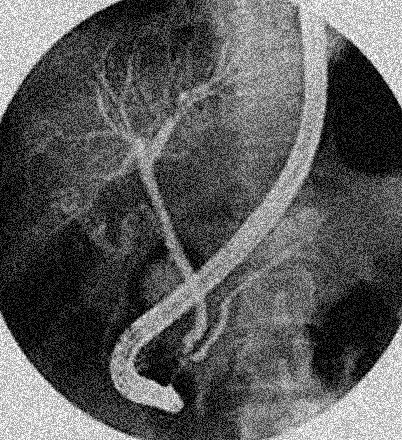

La

cholangio-pancreatographie retrograde par voie endoscopique

(ERCP): Methode invasive pour explore et

traitement de quelquesERCP affections de voie biliaire

: L'endoscopie est en place dans le tube digestif duodenum

D2 par la bouche et insertion un catheter en Teflon

avec guide (0.035) dans ampoule de Vater et guidee a canal

choledoque . Par cette voie on peu opacifie des voies

biliaires par contrast iodique ou de dilatation une portion stenosant de

voie biliaire par le Stent . Technique doit etre

Image radiologique normale

une cholangio-pancreatico retrograde par voie

endoscopique ( ERCP ) . Voies biliaires principale

intra et extrahepatique et canal de Wirsung sont en

voyaient . |